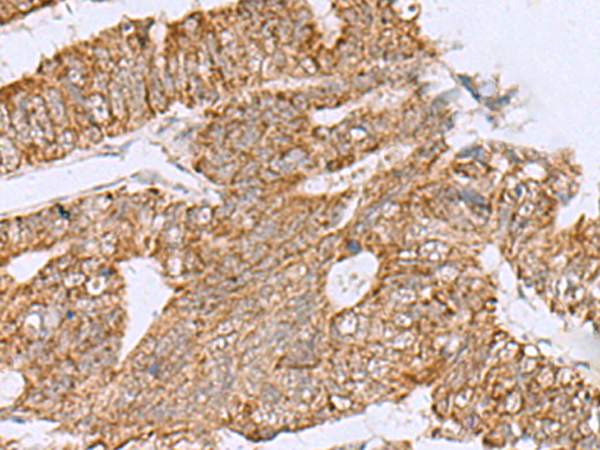

分类: 科研抗体货号: P02993别名: F5F8D; SDNSF; F5F8D2; LMAN1IP应用: IHC反应种属: Human, Mouse, Rat